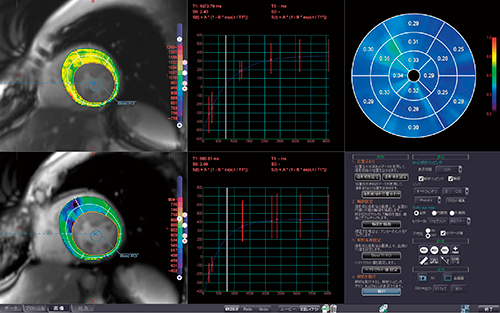

さらに,MR心筋T1マッピングで得られる画素ごとの血液のT1値,ヘマトクリット値を利用して,心筋組織細胞外液分画(extracellular volume fraction:ECV)の定量評価が可能だ。Wongらの報告2)によると,線維化を伴った組織は隙間が正常例に比べて多く,より多くのガドリニウム(Gd)を取り込む。正常のECVは,20〜30%とされ,それ以上になると線維化が進んでいると一般的には言われている。短軸のオーバーレイ表示は,ECVとT1の切り替えを可能とし,全体,内膜側,外膜側での3種類の表示も可能となっている。また,セクター分割機能も備え,1〜12分割までの表示と17セグメント表示を可能としている(図1)。

図1 MR心筋T1マッピング